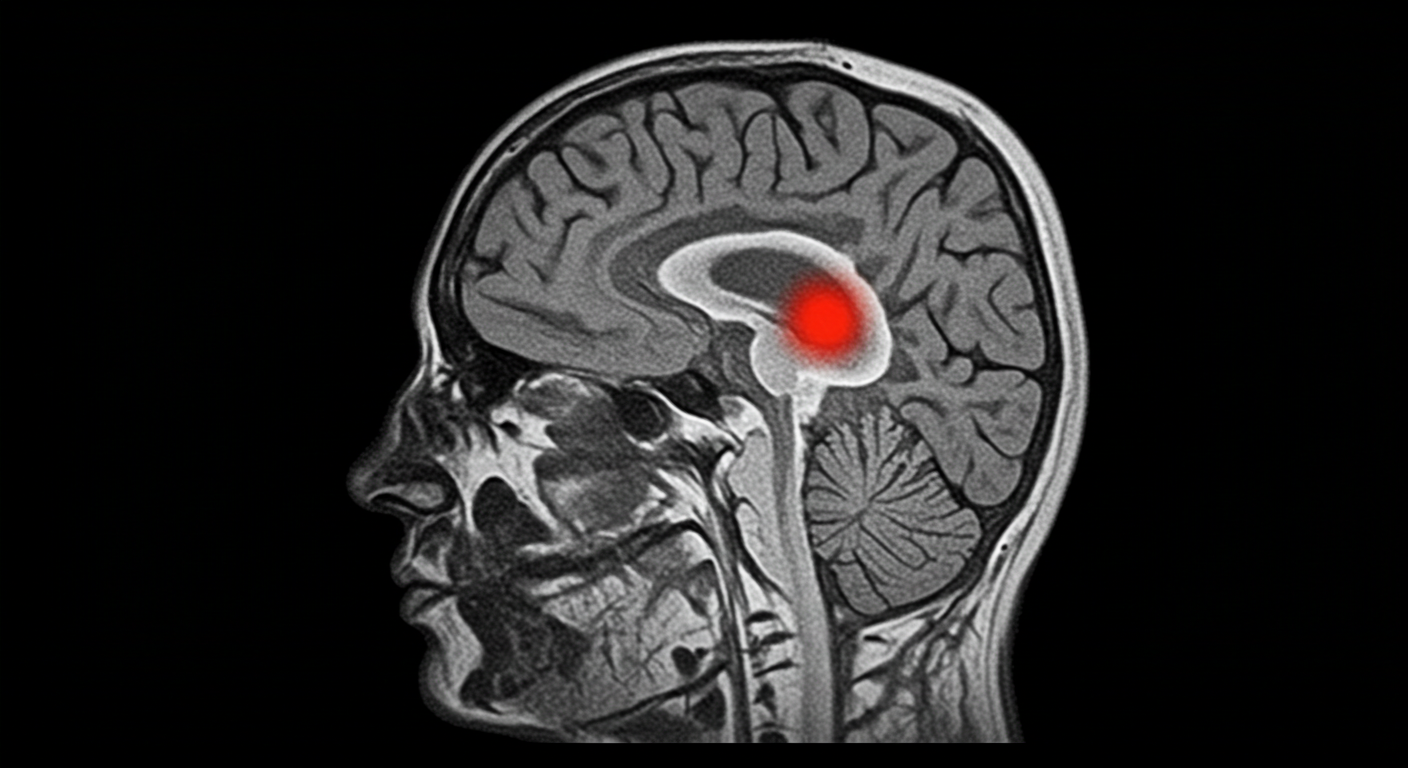

3. 뇌종양

뇌종양은 양성과 악성으로 나뉘며, 조기 발견 시 수술적 치료나 방사선 치료로 완치 가능성이 높습니다. 특히 초기에는 증상이 거의 없어 정기적인 검진이 중요합니다.

MR검사는 자기장과 고주파의 상호작용을 이용하여 인체의 해부학적, 병리학적인 정보를 얻을 수 있는 검사입니다. 뇌 MRI는 치매, 뇌종양 등 뇌의 구조적, 기능적 이상소견 여부를 확인하고자 하는 목적이 있습니다.

- 뇌경색, 뇌출혈, 뇌종양, 치매 등 다양한 질환 진단 가능